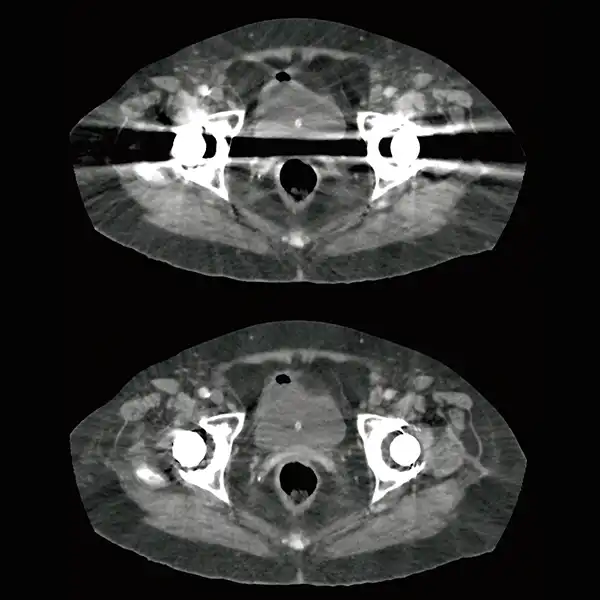

Improve visualization of bone and soft tissue with metal artifact reduction technology SEMAR.

GENESIS Edition’s 16 cm wide area detector signicantly improves your ability to obtain high-quality images for routine and advanced studies. One rotation is all it takes to acquire a whole heart, a neonatal chest, a foot or an ankle exam – in a fraction of a second with less dose and great z-axis uniformity.